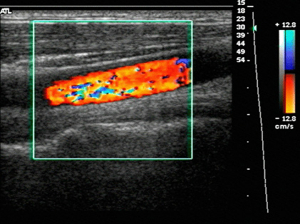

- 도플러 초음파 검사 (Doppler Ultrasound)

- 일반 초음파의 원리에 도플러 효과를 적용한 검사로, 움직이는 혈액의 속도와 방향을 실시간으로 측정할 수 있습니다.

- 혈관 내 혈류의 특성을 분석해 혈류가 정상적으로 흐르는지, 역류나 협착이 있는지 평가할 수 있습니다.

- 혈관의 기능적 상태를 파악하는 데 중요한 역할을 하며, 하지정맥류, 동맥 협착, 혈전 등 혈관 질환 진단에 쓰입니다.